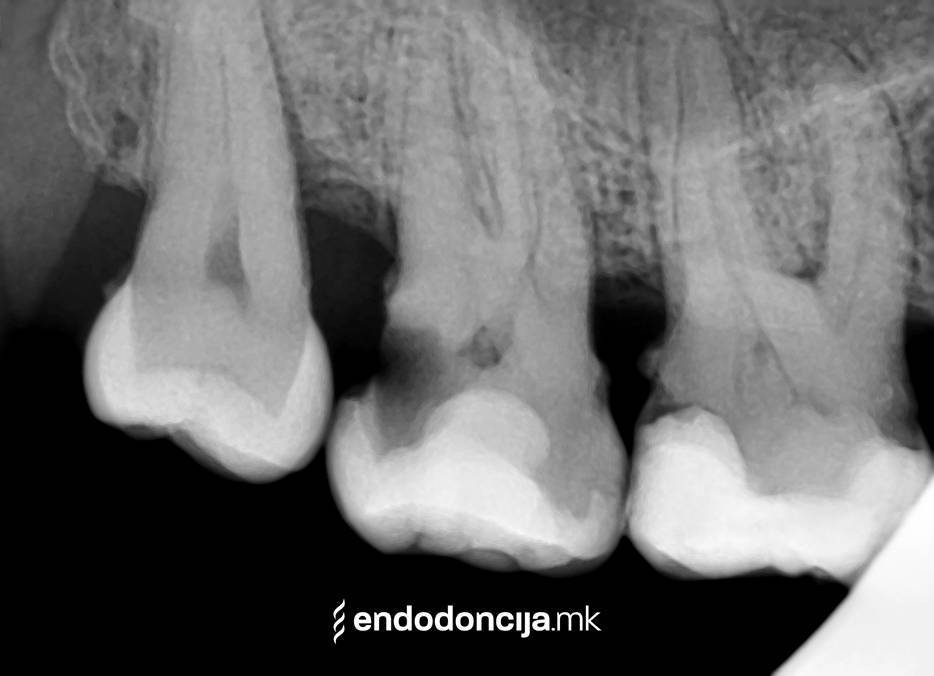

Με τη σωστή θεραπεία, όχι μόνο οι οξείες φλεγμονές αλλά και οι χρόνιες μπορούν επίσης να αντιμετωπιστούν με επιτυχία. Αυτά μπορεί να προκαλέσουν πόνο ή μερικές φορές ακόμη και εντελώς χωρίς συμπτώματα. Η έγκαιρη ανίχνευση και εξάλειψη τέτοιων φλεγμονών είναι ζωτικής σημασίας για τη μακροχρόνια συντήρηση των δοντιών.